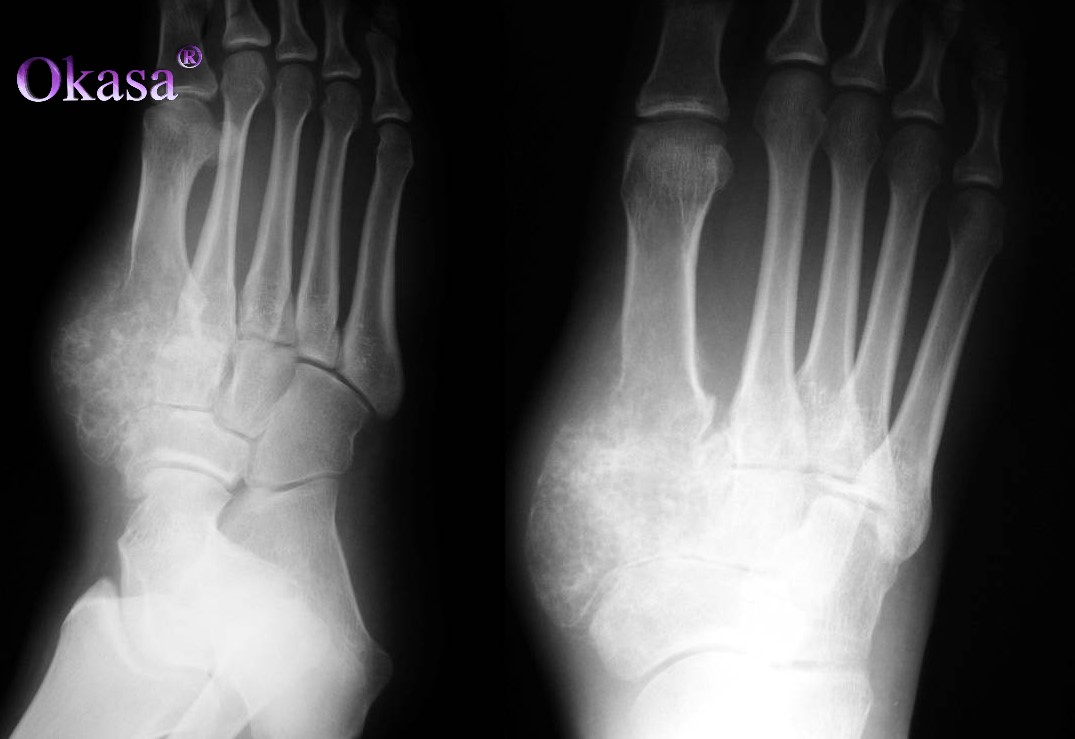

U nội sụn là u xương lành tính thường xuất hiện ở bàn tay, xương bàn tay, xương ngón tay, đầu trên xương cánh tay. U nội sụn xảy ra ở người trong độ tuổi từ 10 – 70 tuổi.

Qua hình ảnh chụp X-quang có thể nhìn thấy xương dài bị tổn thương mở rộng tới thân xương, nhưng không có phản ứng màng xương. Hình ảnh đặc trưng nhìn thấy ở loại u này là các đốm canxi hóa trong nang, đó là những hạt có màu xám trắng, cứng và thấu quang.

U nội sụn là u xương lành tính, nó có thể gây ra các cơn đau nhưng tiến triển chậm và thường không gây ra gãy xương bệnh lý.